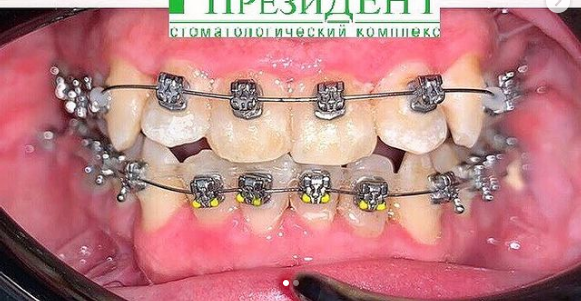

Врач Заводова (Рыбась) Анна Викторовна принимает в стоматологическом комплексе ПРЕЗИДЕНТ НА ЛЮБЛИНСКОЙ в Москве. Имеет рабочий стаж 21 год. Специализируется на ортодонтии, по которой клиника оказывает 3 услуги. Имеет 4 работы до/после в портфолио. Квалификация специалиста подтверждена 15 лицензиями, сертификатами и наградами. Для уточнения дополнительной информации о специалисте или записи на прием можно позвонить по телефону

Установка брекетов

Установка брекетов в Москве

от 200 000 ₽

Снятие брекетов

Снятие брекетов в Москве